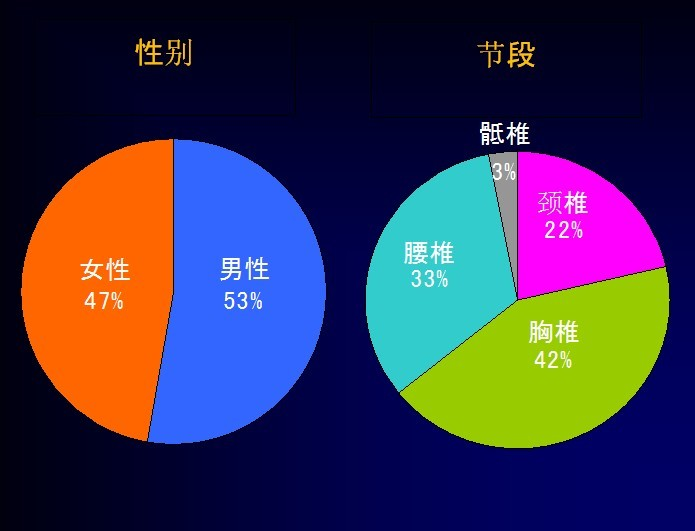

Hiroshi Ozawa等总结分析了674例椎管内肿瘤患者的病例特点:

1.椎管内肿瘤中,硬膜下髓外肿瘤约占所有肿瘤的74%;